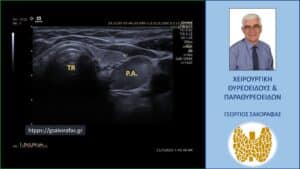

Γιγάντιο αδένωμα παραθυρεοειδούς – με αφορμή ασθενή μας. ΤΗΥ=Θυρεοειδής, P.A.=Αδένωμα παραθυρεοειδούς, CCA=κοινή καρωτίδα αρτηρία, ESOPH=οισοφάγος, TR=τραχεία, RL=δεξιός λοβός θυρεοειδούς LL=αριστερός λοβός θυρεοειδούς. Με το κίτρινο βέλος επισημαίνεται το αριστερό παλίνδρομο λαρυγγικό νεύρο

Στο υπερηχογράφημα απεικονίσθηκε πίσω από τον αριστερό λοβό ευμέγεθες μόρφωμα με διαστάσεις 45 x 12 mm και ηχομορφολογία συμβατή με αδένωμα παραθυρεοειδούς. Βρίσκεται επί τα εκτός της τραχείας, αντίστοιχα προς την 2η προς 3η ώρα αυτής, επί τα εντός και οπισθίως της αριστερής κοινής καρωτίδας και σε μικρή απόσταση από το αριστερό όριο του οισοφάγου.

Εκτείνεται κατά μήκος του μεγαλύτερου μήκους του αριστερού λοβού του θυρεοειδούς.

Απεικόνιση του αδενώματος στο υπερηχογράφημα – επιμήκης διατομή

Απεικόνιση του αδενώματος στο υπερηχογράφημα – εγκάρσια διατομή